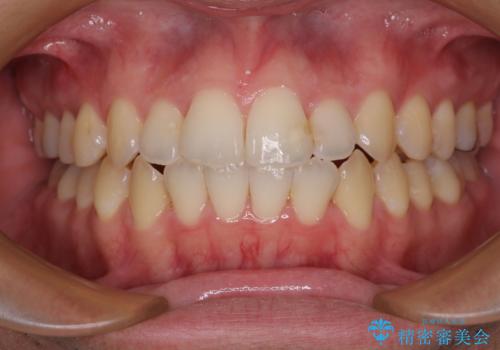

ディープバイトと叢生 インビザラインによる矯正治療

- 前歯のディープバイトと叢生を気にして来院された患者様です。

ディープバイトもデコボコも改善され、気になっていた銀歯もセラミックとなり、患者様には大変満足していただきました。